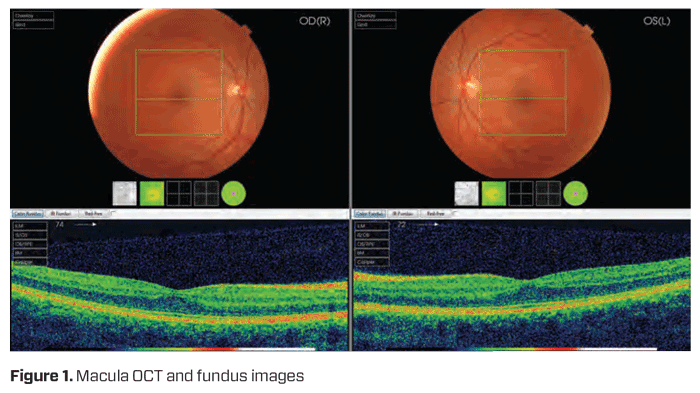

She was sent for magnetic resonance imaging (MRI) to investigate further. The consultant radiologist reported that the MRI (Figure 3) showed ‘somewhat prominent’ extraocular muscles but still ‘symmetrical in appearance and position.’ They hypothesised Graves’ disease, introducing a new differential diagnosis, however, blood tests did not confirm any active thyroid levels. The patient no longer wanted to be reliant on any level of prism correction so decided to proceed with surgical intervention–strabismus surgery.

Staphyloma prevalence increases with axial length, however they may still be present in eyes with axial lengths below 26.5mm.8 In this case, interestingly, the patient had normal axial lengths and the absence of a posterior staphyloma on fundus examination (Figure 1) as well as an absence of equatorial staphyloma on MRI (Figure 3), therefore ruling out KES and HES as potential diagnoses.